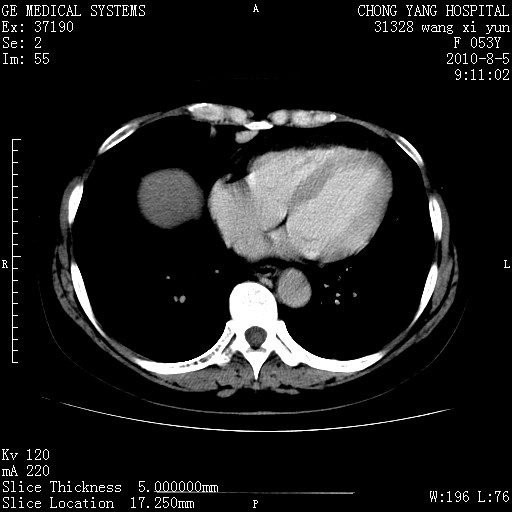

标题: CT28214:F41Y 血尿二十天,建议盆腔平扫加增强。

胆管细胞ca?

1)考虑肝左叶胆管细胞癌。2)脂肪肝。

支持胆管细胞ca。